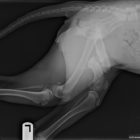

The injury she suffered was pretty bad, and it was never properly cared for, so she will need a plate in her hip to fix the fracture and help her to be able to walk and not be in pain. The other option is amputation. The cost of the surgery is $2,200 – $2,400, plus any pre- and post-surgery care.